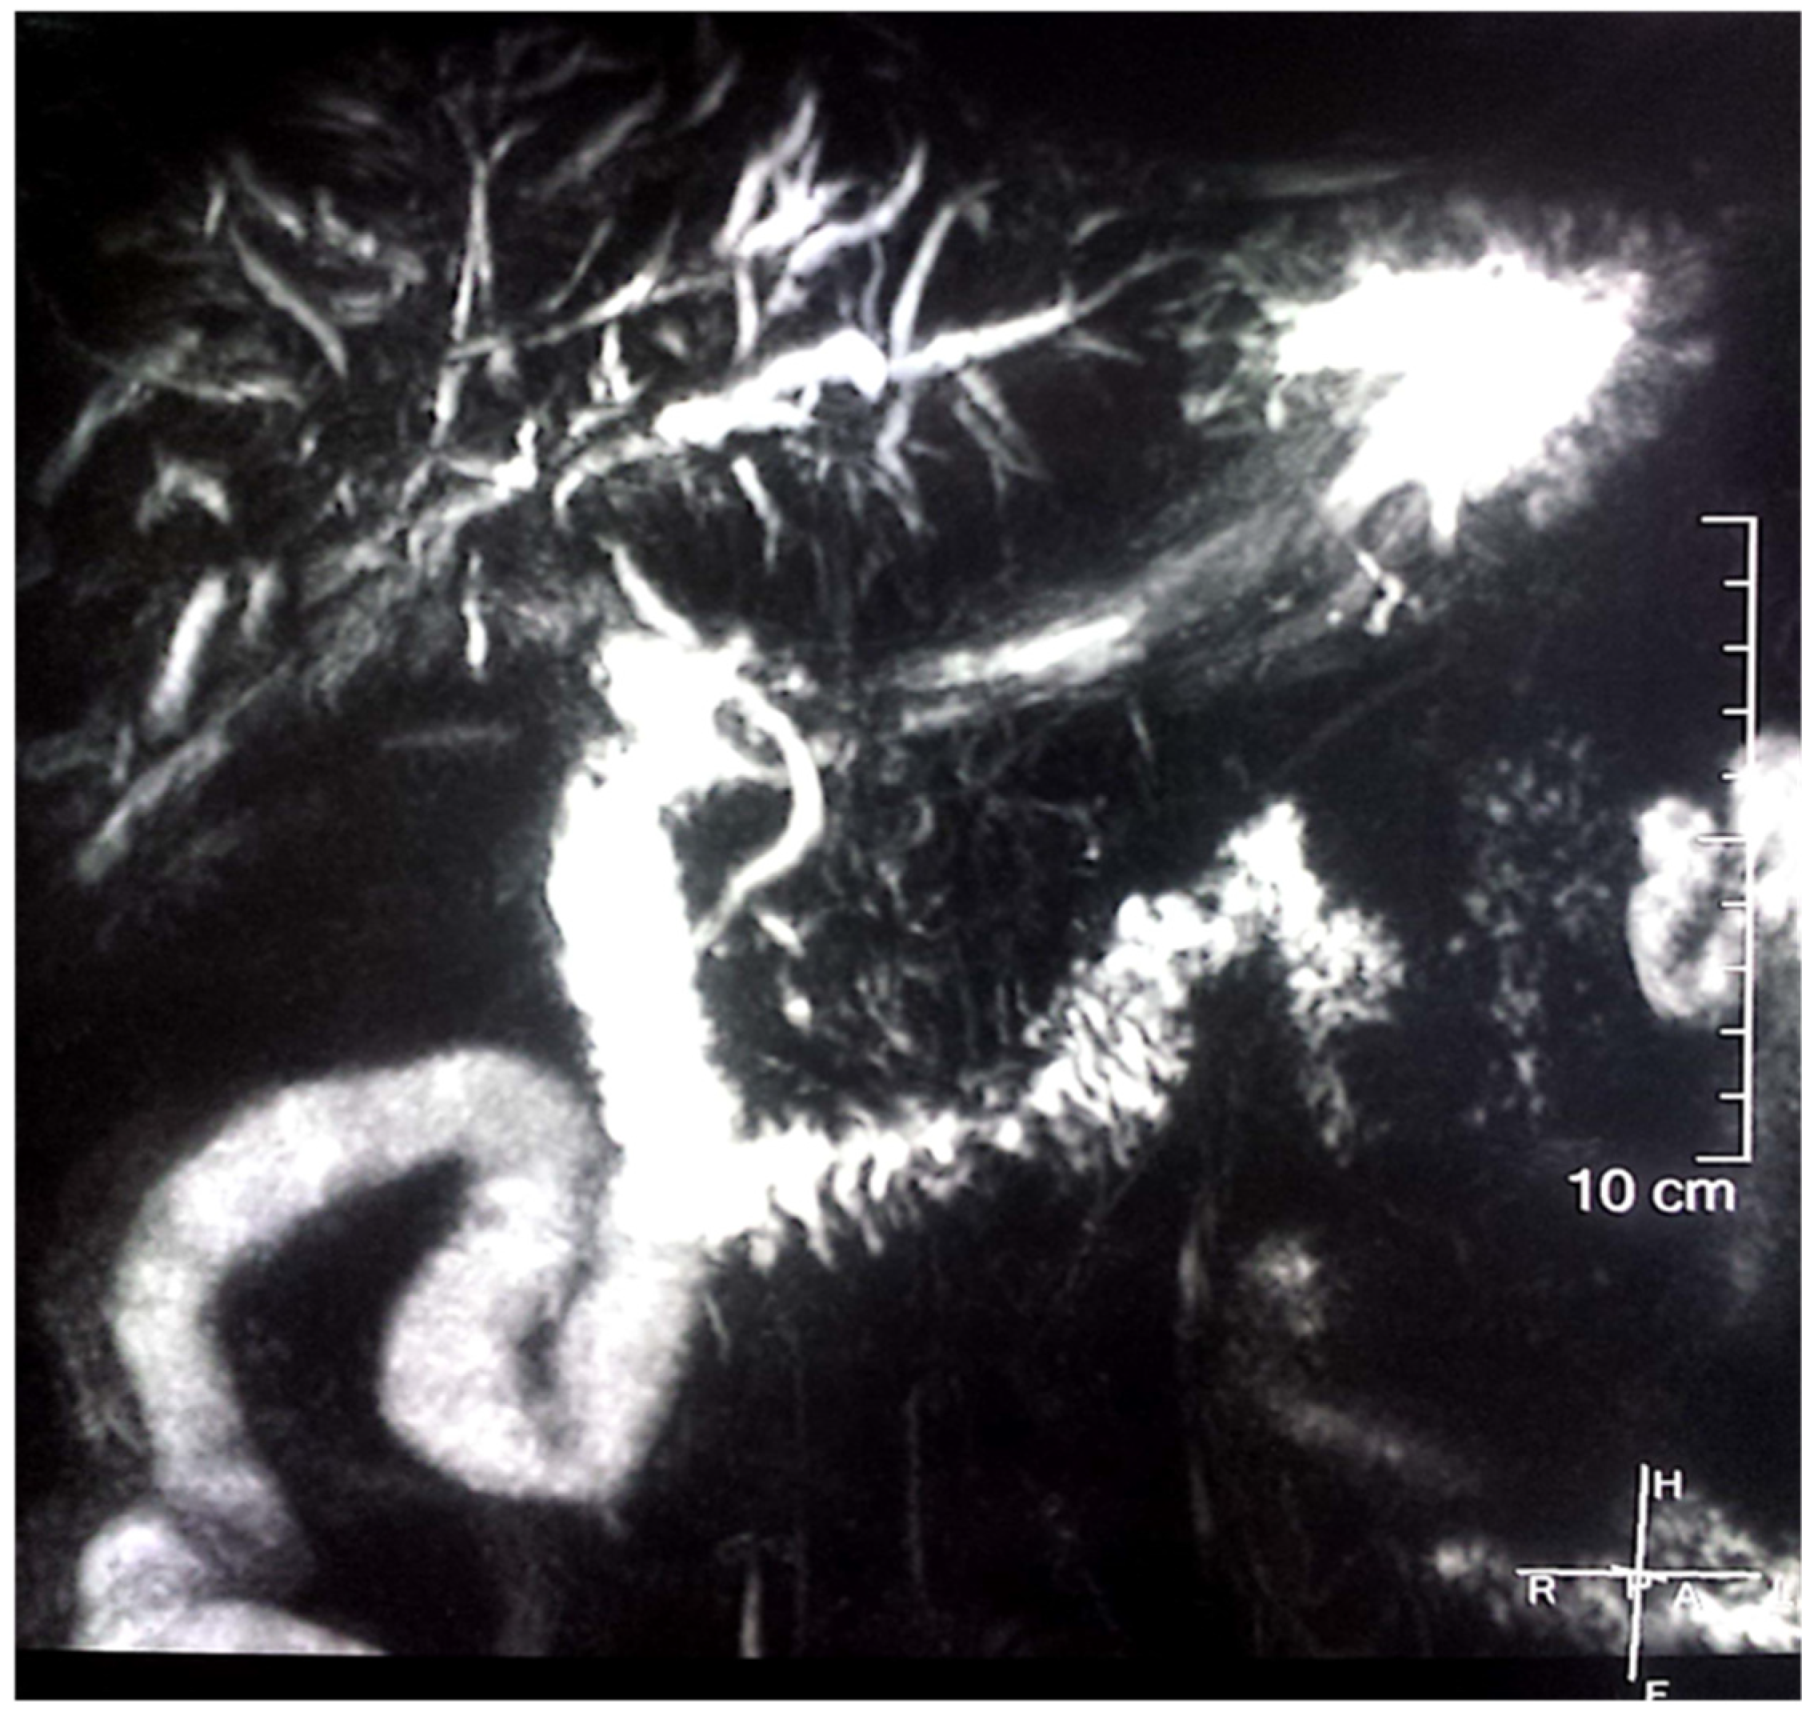

2. Case Report